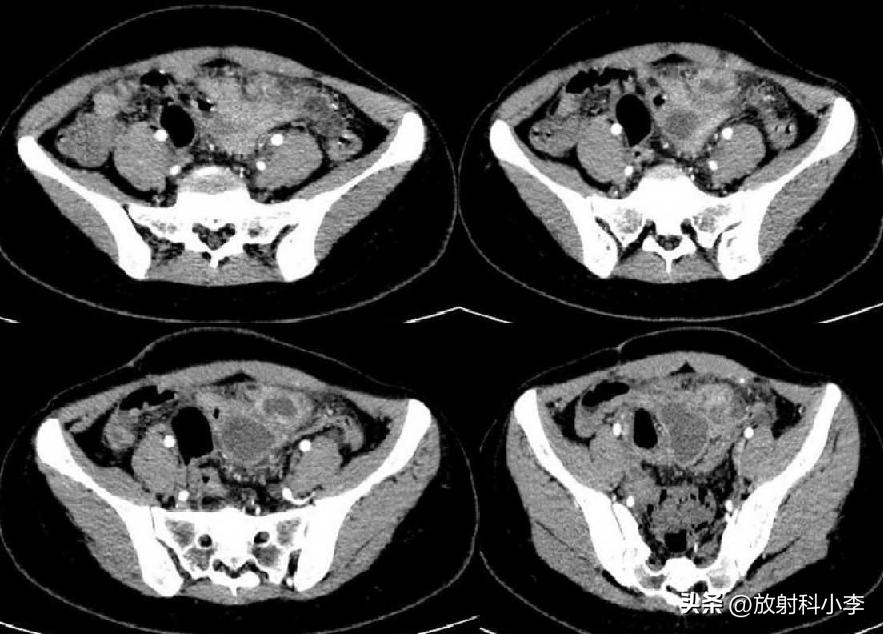

case 1. F,42Y,突发右下腹痛半天

CT:右侧附件区见一混杂密度肿块,可见脂肪密度,肿块壁增厚,与子宫之间的连接结构增粗、稍扭曲,密度不均匀。考虑右卵巢畸胎瘤蒂扭转。